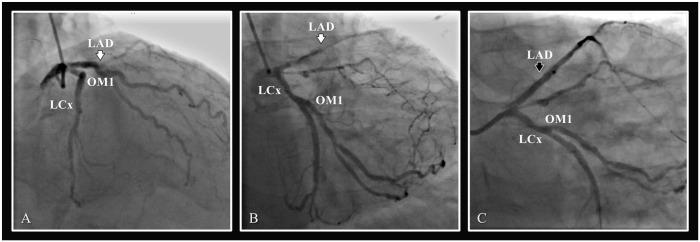

Drug-eluting stents (DES) have superior efficacy compared with bare metal stents (BMS) for treatment of coronary artery lesions. However, BMS continue to play an important role in percutaneous coronary intervention for patients who are at a high bleeding risk, because they require a shorter duration of dual antiplatelet therapy. However, new developments in DES and understanding of the optimal time required for dual antiplatelet therapy after percutaneous coronary intervention may further limit the use of BMS. Furthermore, the use of dual antiplatelet therapy is complicated in patients with cirrhosis, who may have coagulopathy. In this article, we present the case of a patient with cirrhosis and end-stage chronic liver disease with coronary artery disease and a proximal left anterior descending stenosis who received a DES and had multiple episodes of gastrointestinal bleeding. We review the literature addressing DES and BMS in patients at high risk of bleeding. We also review the optimal duration of dual antiplatelet therapy.

药物洗脱支架 (DES) 在治疗冠状动脉病变方面优于裸金属支架 (BMS)。然而,对于出血风险较高的患者,BMS 在经皮冠状动脉介入治疗中仍发挥着重要作用,因为它们需要较短时间的双联抗血小板治疗。然而,DES 的新进展和对经皮冠状动脉介入治疗后双联抗血小板治疗所需的最佳时间的理解可能会进一步限制 BMS 的使用。此外,在可能患有凝血功能障碍的肝硬化患者中,双联抗血小板治疗的使用较为复杂。本文介绍了一位患有肝硬化和终末期慢性肝病、伴有冠状动脉疾病和左前降支近段狭窄的患者,该患者接受了 DES 治疗并多次出现胃肠道出血。我们回顾了文献中关于高出血风险患者的 DES 和 BMS 的内容。我们还回顾了双联抗血小板治疗的最佳时间。